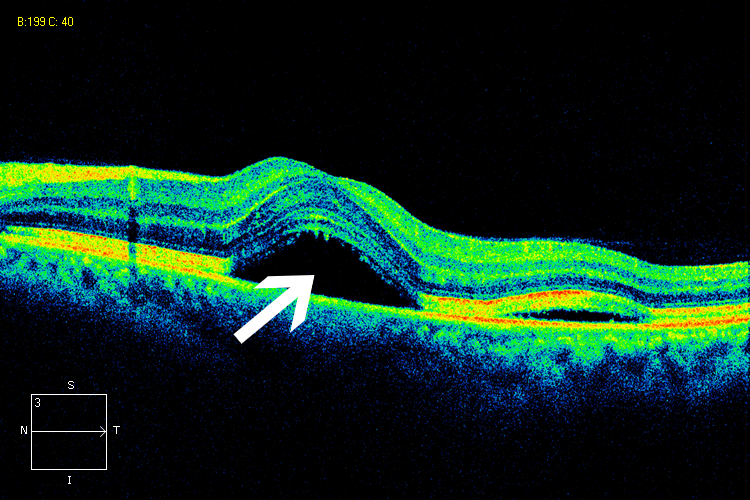

高度近视眼底病变合并脉络膜新生血管

眼科ab超检查单怎么看常见眼底疾病检查结果的秒懂解读_https://www.jmylbn.com_新闻资讯_第7张此疾病出自高频语句,“眼底新长血管了,得往眼珠子里打针”。

眼科ab超检查单怎么看常见眼底疾病检查结果的秒懂解读_https://www.jmylbn.com_新闻资讯_第30张

OCT:黄斑区脉络膜新生血管表现为一个隆起的小鼓包

图片来源:天津市眼科医院